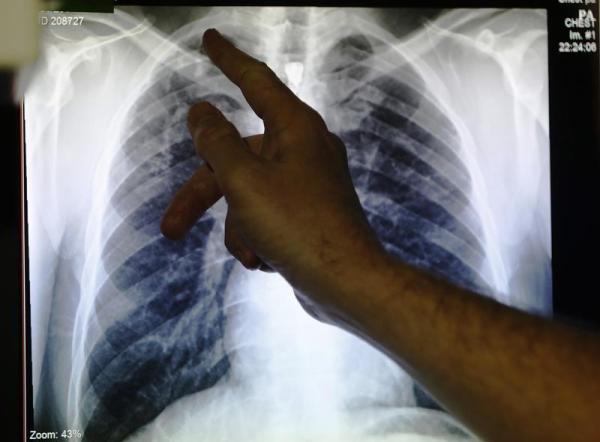

GENEVA, Oct 28 — Global deaths from tuberculosis are estimated to have increased between 2019 and 2021, reversing years of decline as the Covid-19 pandemic severely derailed efforts to tackle the disease, the World Health Organization said on Thursday.

WHO’s annual TB report estimates that tuberculosis killed 1.6 million people in 2021, above the estimated 1.5 million deaths in 2020, and 1.4 million deaths in 2019. Deaths related to tuberculosis had fallen between 2005 and 2019.

About 10.6 million people were infected with tuberculosis in 2021, an increase of 4.5 per cent from 2020, according to the WHO report.